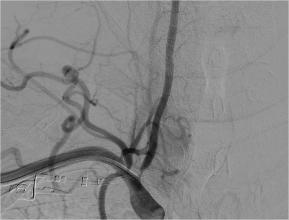

予行支架置入术后狭窄明显改善

胡先生入院后,脑病科随即为他进行中医特色治疗,并行脑血管造影,提示右侧椎动脉重度狭窄、左侧大脑前动脉闭塞,与其沟通后行右侧椎动脉重度狭窄支架植入术,术后恢复良好,配合中医特色治疗5天后,胡先生就出院了,出院时未出现左侧肢体无力,左侧肢体灵活,无明显头晕、眼花,左侧面部麻木症状消失,无明显指端冰凉,入院时存在的症状基本消失,达到基本痊愈的标准。